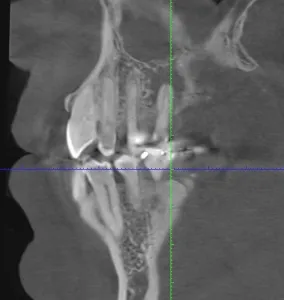

It amazes us how well people can heal sometimes. This case, done by Dr. Wes Parker, involved a 45 year old male who was referred for a carious, necrotic (dead) tooth #14 (upper left first molar). The patient also reported left sided sinus pressure and drainage. At his consultation, we obtained a Cone Beam CT (CBCT) scan. On his CBCT, you could see where the infection and inflammation from tooth #14 had eroded through the floor of the left maxillary sinus. We discussed this with him and scheduled surgery shortly after the consultation. Dr. Parker removed tooth #14, cleaned out the pus and inflamed maxillary sinus lining through the socket. The inflamed, thickened sinus lining went almost up to the orbit (eye socket). Dr. Parker then closed off the sinus communication. Following this, Dr. Parker placed a bone graft over the sinus closure, and then sutured over that to close the wound. The patient healed very well. He was compliant with the sinus precautions and medications that were prescribed. Next, Dr. Parker proceeded with implant placement in the #14 site with a simultaneous indirect sinus lift or “sinus bump.” The implant placement surgery went well, and after about 5 months of healing time, the patient received a crown on the implant from his dentist. Image #1 is a preoperative PA radiograph of the carious, necrotic, nonrestorable tooth #14 (upper left first molar). Image #2 is a coronal slice from the patient’s preoperative CBCT showing the necrotic tooth #14 with a periapical radiolucency and maxillary sinus inflammation stemming from the necrotic tooth. Image #3 is a sagittal slice from the patient’s preoperative CBCT showing the necrotic tooth #14 with a periapical radiolucency and maxillary sinus inflammation stemming from the necrotic tooth. Image #4 is a sagittal CBCT slice from the patient’s post extraction CBCT showing resolution of the sinus inflammation and measurements for the future dental implant. Image #5 is an immediate postoperative PA of the implant in the #14 site following implant placement with a simultaneous indirect sinus lift. Image #6 is a 5 month postoperative PA showing the healed, integrated implant prior to crown placement with a healed sinus lift bone graft above it and no sinus inflammation.